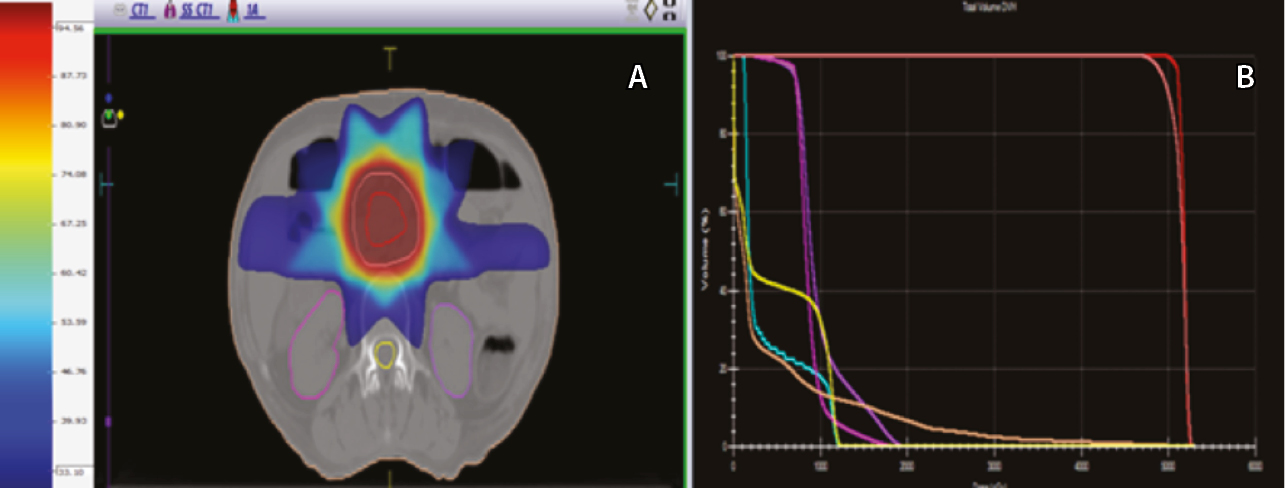

Конформную дистанционную ЛТ проводили на линейном ускорителе Elekta Axesse (Elekta, Швеция) с энергией 6 МэВ в многопольном статическом режиме через поля сложной конфигурации. Облучение осуществляли в режиме дневного дробления дозы: РОД 2 Гр 2 раза в день с интервалом 6 часов. Всего проведено 25 сеансов, в том числе один – в последний день. Режим фракционирования: 5 раз в неделю, продолжительностью 13 дней, до физической СОД 50 Гр, что эквивалентно 62 Гр обычного облучения по линейно-квадратичной модели для α/β 2,5 Гр (рис. 3).

Рис. 3. Пациент П., 79 лет, диагноз: рак головки поджелудочной железы. Дозиметрический план лучевой терапии. А – объемы облучения (аксиальная плоскость). В клинический объем облучения (CTV, красная линия) включен истинный размер опухоли. Планируемый объем облучения (PTV, розовая линия) составляет контур с отступлением на 1 см по всем направлениям от сформированного CTV из-за погрешности смещения органов при дыхании. На шкале представлены цветовые обозначения дозного распределения. Б – дозо-объемные распределения на облучаемые органы и ткани: планируемый объем облучения (PTV, розовая линия), клинический объем облучения опухоли (CTV, красная линия) составляет 50 Гр; лучевая нагрузка на соседние органы не превышает стандартные ограничения: средние дозы на спинной мозг (желтая линия) < 15 Гр и на почки (два оттенка фуксии) < 20 Гр